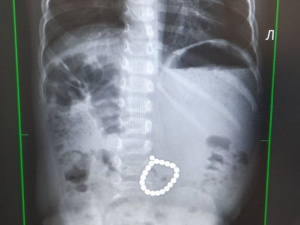

На днях в ММЦ "Северный" поступил двухлетний пациент, мама которого пояснила, что малыш съел металлическую часть от электромашинки. Приехавшие врачи скорой помощи забрали ребёнка для обследования в больницу, где малышу немедля провели рентгенографию грудной клетки и брюшной полости.

"Полученные результаты поразили медиков - на снимке врачи обнаружили металлические округлые образования, сложенные в виде браслета. Было решено оставить мальчика для динамического наблюдения в хирургическом отделении", - сообщили в медучреждении. В надежде, что инородное тело будет дальше продвигаться по кишечнику и выйдет самостоятельно, врачи провели несколько дней. Но исследование показывало, что образование остается на прежнем месте. Не удалось его обнаружить и при помощи эндоскопических методов. В итоге медики приняли решение провести операцию.

"Ребенка подготовили к диагностической лапараскопии. Но последовательный осмотр органов брюшной полости при помощи лапароскопа, подключенного к видеосистеме, не дал нам ожидаемых результатов. Ни обнаружить, ни извлечь магниты через небольшой лапаротомный разрез нам не удалось. Поэтому операционной бригаде пришлось перейти на открытую операцию - лапаратомию. И только тогда в начальном отделе тонкой кишки нам удалось обнаружить плотные образования. Мы вскрыли просвет тонкой кишки и нашли цепочку магнитиков", - рассказывает детский хирург Николай Шеметов, заведующий хирургическим отделением ММЦ "Северный".

Благодаря своевременной помощи врачи вовремя обнаружили в организме опасную находку. Кроме того, ребёнку повезло, что магниты были связаны в браслет, поэтому они не расцепились и не попали в разные петли кишечника. Все это позволило избежать критических последствий и буквально спасти жизнь маленькому пациенту. Сейчас малыш чувствует себя хорошо и идёт на поправку.